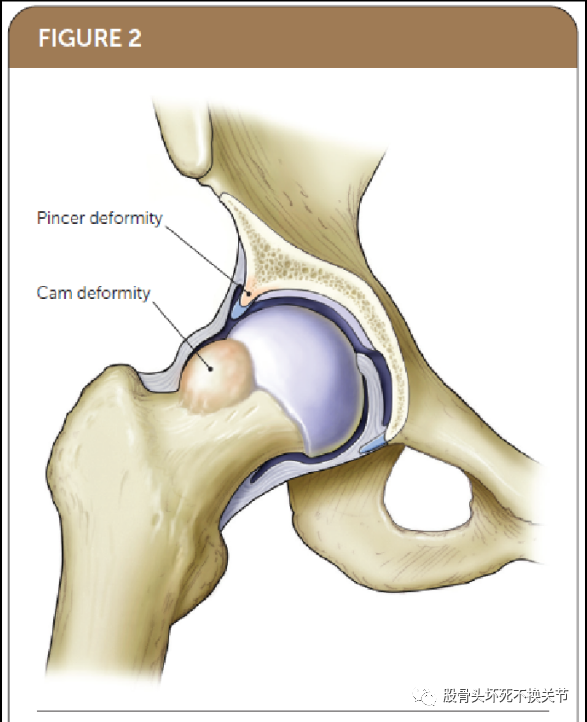

屈曲-内收-内旋试验(Flexion-Adduction-Internal Rotation,FADDIR)

这个激惹性方法用来评估FAIS和盂唇损伤(表1)。

这种现象最早是由Reinhold Ganz在FAIS的早期描述中提到的[18]。其主要阐述了在仰卧和健侧卧位的检查。检查者被动屈曲、内收和内旋患者的髋关节(图4)。整个过程中患者反复疼痛则认为是阳性体征并明确FAIS诊断[16,19,20]。

一项对有症状髋关节疼痛患者的研究评估了前方撞击试验和FADDIR 试验的有效性,两项试验有效性均为80% ,然而,它们的诊断特异性较低,分别为26%和24% [21]。通常在整个运动范围内进行一系列组合动作的体格检查是最好的方法,在屈髋内收内旋检查时施以压力,以引发潜在的不适症状。当髋关节屈曲90°;进行这些特殊检查时,这种方法有时被称为前方撞击试验[16,22]。前方撞击试验检查FAIS的灵敏度在60%~100%之间,检查者的一致性优于96% [14,16,23,24]。